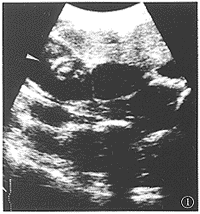

图1 右上腹斜切面。右肾(箭头)内侧见一肿物。其回声均匀,边界清晰且较规则,随呼吸可上下移动。术后病理证实为腹膜后节神经瘤。